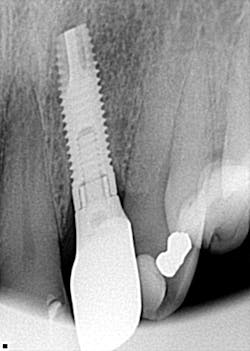

CAN YOU REALLY IDENTIFY more than 900 dental implants by looking at a single radiograph? I got my answer to this question when a patient came in and needed his lower fixed hybrid prosthesis removed. That bad boy had been on there for a long time and was, quite frankly, nasty! The problem? There was no record of who placed the implants or which dental implant system was in place. What did I do? Well, what do others do when they are faced with the same dilemma? You can read about it at this link; you may be surprised at just how much information a single radiograph can give you!